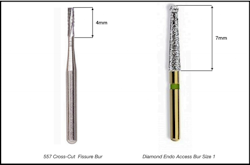

Target vertical depths and terminal depth estimates only have value when used in conjunction with a method to gauge depth. Two methods are available. One method involves the use of a bur with known length dimensions. Many different types of burs can be used to create an initial endodontic access. The active cutting surfaces of straight carbide-fissure burs and/or straight diamond coated burs have consistent measurable lengths that can be used as reference (Fig. 4).